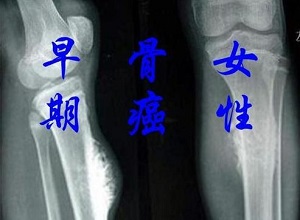

郑州中医肿瘤医师王卫昌说:得了骨癌身体会有4个表现,越早发现越好.虽然目前的医疗条件比较好,但癌症的治疗仍然比较困难,因为与其他疾病不同,癌症不仅会逐渐加重病情,而且会转移,非常善于隐藏。因此,即使通过手术治疗,也很难有效地清除癌症,这对人体健康非常有害。

不知道大家是否听说过骨癌。许多骨癌患者是由于长期炎症无法改善而引起的,但骨转移也会导致骨癌。然而,当骨癌发生时,会有一些明显的变化。如果患者能及时注意并改善,也能达到有效的治疗效果。

患有骨癌,身体常有哪四种表现?

一个身体表现是关节肿胀不适,骨科医生说,正常人一般不容易出现关节骨肿胀不适,但如果创伤或冷湿因素也会导致骨关节肿胀不适,但当不明原因的骨肿胀时,应保持警惕。

因为当患者患有骨癌时,体内的癌细胞会继续生长,导致骨肿胀,甚至导致人体变形,大大降低骨骼发育速度。当它发生在下肢时,这种症状会更加严重。为了避免病情恶化,需要及时检查和早期治疗。

第二种身体表现是受外力影响,容易出现骨折症状。当骨癌发生时,癌细胞会不断地损伤骨骼,这很容易导致骨折症状。骨折可能发生在外部压力下,骨折部位会更加疼痛,肿胀会加剧,严重的患者会瘫痪。

因此,我们必须警惕生活中频繁的骨折或骨关节损伤。它很可能是由骨癌引起的。一些骨癌患者在日常生活中行走时会受到很大影响。严重的骨关节疼痛和不适不利于人体健康。

第三种身体表现是出现发烧的症状。骨癌不仅会导致骨关节疼痛、肿胀等不适反应,还会导致患者发烧。如果他们在生活中不受风寒的影响,并且经常发烧,他们应该怀疑这是否是由骨癌引起的。

发烧是骨癌患者常见的症状,通常发烧程度较低。然而,随着病情的加重,发烧的程度会增加。即使药物治疗能有效缓解,也容易复发,引起人体不适。

第四种身体表现是触摸时可发现异常肿块。当骨癌发生时,很容易引起骨关节疼痛、肿胀和不适,尤其是在骨膜或表皮较浅的部位。触摸骨关节时,很容易接触到肿块,这也是骨癌发生时的明显信号。

郑州御和堂中医师提醒大家,骨癌必须及时发现和治疗。如果出现上述四种异常疾病,应立即到医馆检查,并采取预防措施。